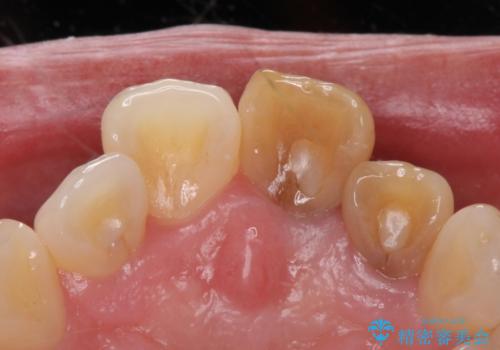

歯は根管治療が終了して時間が経つとだんだん茶色く変色していきます。

色調はクラウン修復により改善され、歯並びも術前より改善されたことで大変喜んでいただけました。